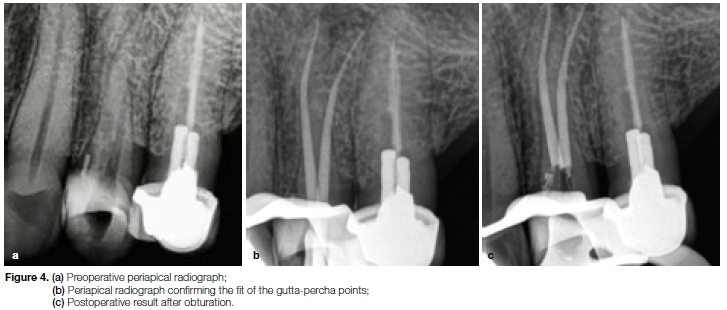

Case report

The patient, a 32 year old male presented with a history of an emergency root canal treatment on his maxillary right first premolar (Figure 4a). After glide path preparation with a One G instrument (Micro-Mega, Besançon, France) both root canal systems were prepared with the OneShape (25/06) instrument. Figures 4b illustrates the cone-fit radiograph to confirm the fit of two size 25/06 gutta-percha points. The final result after root canal obturation is shown in Figure 4c.